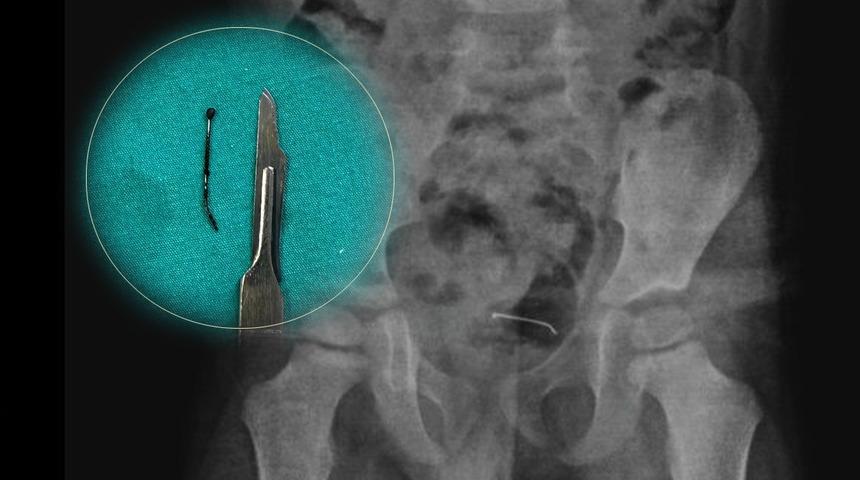

Tatvan Devlet Hastanesi'nde yapılan röntgen incelemelerinde, mesane duvarında metal bir cismin olduğu tespit edildi. Yapılan muayenede, 3 santimetre boyutundaki toplu iğnenin mesane duvarına yapıştığı ortaya çıktı. Ameliyat kararı veren Çocuk Cerrahi Uzmanı Op. Dr. Tahsin Onat Kamçı, başarılı bir operasyonla, aylardır vücutta kalmış olan tehlikeli cismi başarıyla çıkardı.

Kamçı, operasyon sonrası yaptığı açıklamada, "Çocuğun vücudundaki cisim doğal yollarla atılmadı, bu yüzden ameliyat kararı aldık. Cismin mesane duvarına yapıştığını gördük ve cerrahi müdahale ile toplu iğneyi çıkardık. Şu an genel sağlık durumu iyi, kendisini taburcu ettik." dedi.